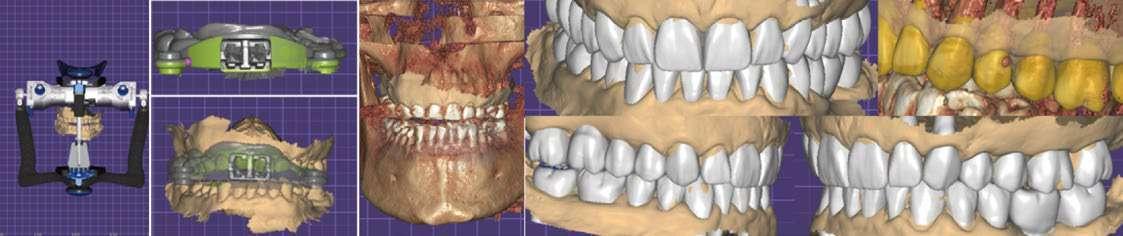

Registros y planificación digital

Se recopilaron registros clínicos como fotografías extraorales e intraorales (Fig. 1–6) y digitales completos, incluyendo escaneados intraorales y registros de movimientos mandibulares. Los datos se integraron en un articulador virtual mediante el software de diseño digital (Exocad), montando los modelos maxilares, archivo de movimientos mandibulares y horquilla en formato STL.

Encerado diagnóstico

Se realizó un encerado diagnóstico digital orientado a restablecer la morfología dental bajo criterios estéticos y funcionales. La incorporación de los registros mandibulares permitió ajustar el diseño a los movimientos dinámicos del paciente, evitando interferencias y contactos prematuros.

Determinación de la Dimensión Vertical en Oclusión (DVO)

Se planificó un aumento de ambas arcadas. La nueva dimensión vertical de oclusión (DVO) se determinó mediante un arco gótico y se validó con registros de movimientos laterales y protrusivos obtenidos con el sistema Zebris (Fig. 7–9). Y se procedió a realizar un CBCT con arco gótico colocado para validar la posición intermaxilar.

Planificación del tratamiento

Se estableció un tratamiento combinado:

1. Ortodoncia Invisalign Go™: corrección de apiñamiento inferior, aumento de resalte y optimización de márgenes gingivales.

2. Rehabilitación protésica: carillas anteriores e incrustaciones de disilicato de litio, junto con puentes posteriores en zirconia monolítica (1.5–1.7 y 3.5–3.7).

3. Provisionalización posterior con técnica de composite estampado y guías de silicona transparente (Fig. 10–21).

Provisionalización y planificación ortodóncica

Se decidió provisionalizar únicamente el sector posterior (Fig. 22-24), en lugar de ambos sectores (anterior y posterior), con el objetivo de facilitar el espacio necesario para los movimientos ortodóncicos y desbloquear el sector anterior, permitiendo así una mayor libertad de desplazamiento dental. El paciente fue informado previamente de que, durante la fase ortodóncica, presentaría una mordida abierta anterior y provisionales posteriores de larga duración. Asimismo, se le explicó que al finalizar el tratamiento se observarían diastemas en los incisivos superiores, consecuencia de la inclinación vestibular planificada, considerando que dichos dientes serían posteriormente restaurados. Para la colocación de los provisionales de composite se empleó un sistema adhesivo autograbante con grabado selectivo del esmalte, con el fin de evitar sensibilidad postoperatoria y lograr un sellado inmediato de la dentina, dado el grado de exposición re-

Figura 7-9. Registros tomados mediante uso de un arco gótico digitalmente diseñado junto con registro de movimientos dinámicos.

Figura 10-17. Encerado digital para guiar el tratamiento ortodóntico y restaurador.

Figura 18-21. Provisionalización con técnica de estampado.

sultante del desgaste severo. Una vez establecida la provisionalización de larga duración y determinada la nueva dimensión vertical de oclusión, se tomaron los registros necesarios para iniciar la fase de alineación ortodóncica con el sistema Invisalign Go™. Dichos registros incluyeron escaneados intraorales de ambas arcadas y una secuencia fotográfica completa obtenida mediante la aplicación Invisalign PracticeApp®.

Tratamiento ortodóncico

A través de la planificación digital en el ClinCheck® Software, se determinaron los movimientos ortodóncicos indicados, que incluyeron: aumento del resalte, corrección del apiñamiento inferior y una combinación de intrusión y extrusión con el objetivo de nivelar márgenes gingivales. Todos estos mo-

vimientos fueron diseñados considerando la fase restauradora posterior. El resultado de la planificación digital de los movimientos ortodóncicos obtuvimos: 19 alineadores en total, 7 superiores y 19 inferiores, los cuales se indicaron cambios cada 7 días como recomienda la casa comercial y se le explicó al paciente la importancia de utilizar los alineadores entre 20 a 22 horas al día. En dicha planificación también se aplicaron ataches estratégicos y se realizaron desgastes interproximales (IPR 0,2–0,3 mm). Se realizaron controles periódicos cada 4 alineadores, en los cuales observamos mejoras progresivas del apiñamiento inferior y la generación controlada de diastemas superiores tal como los planificamos en el software.